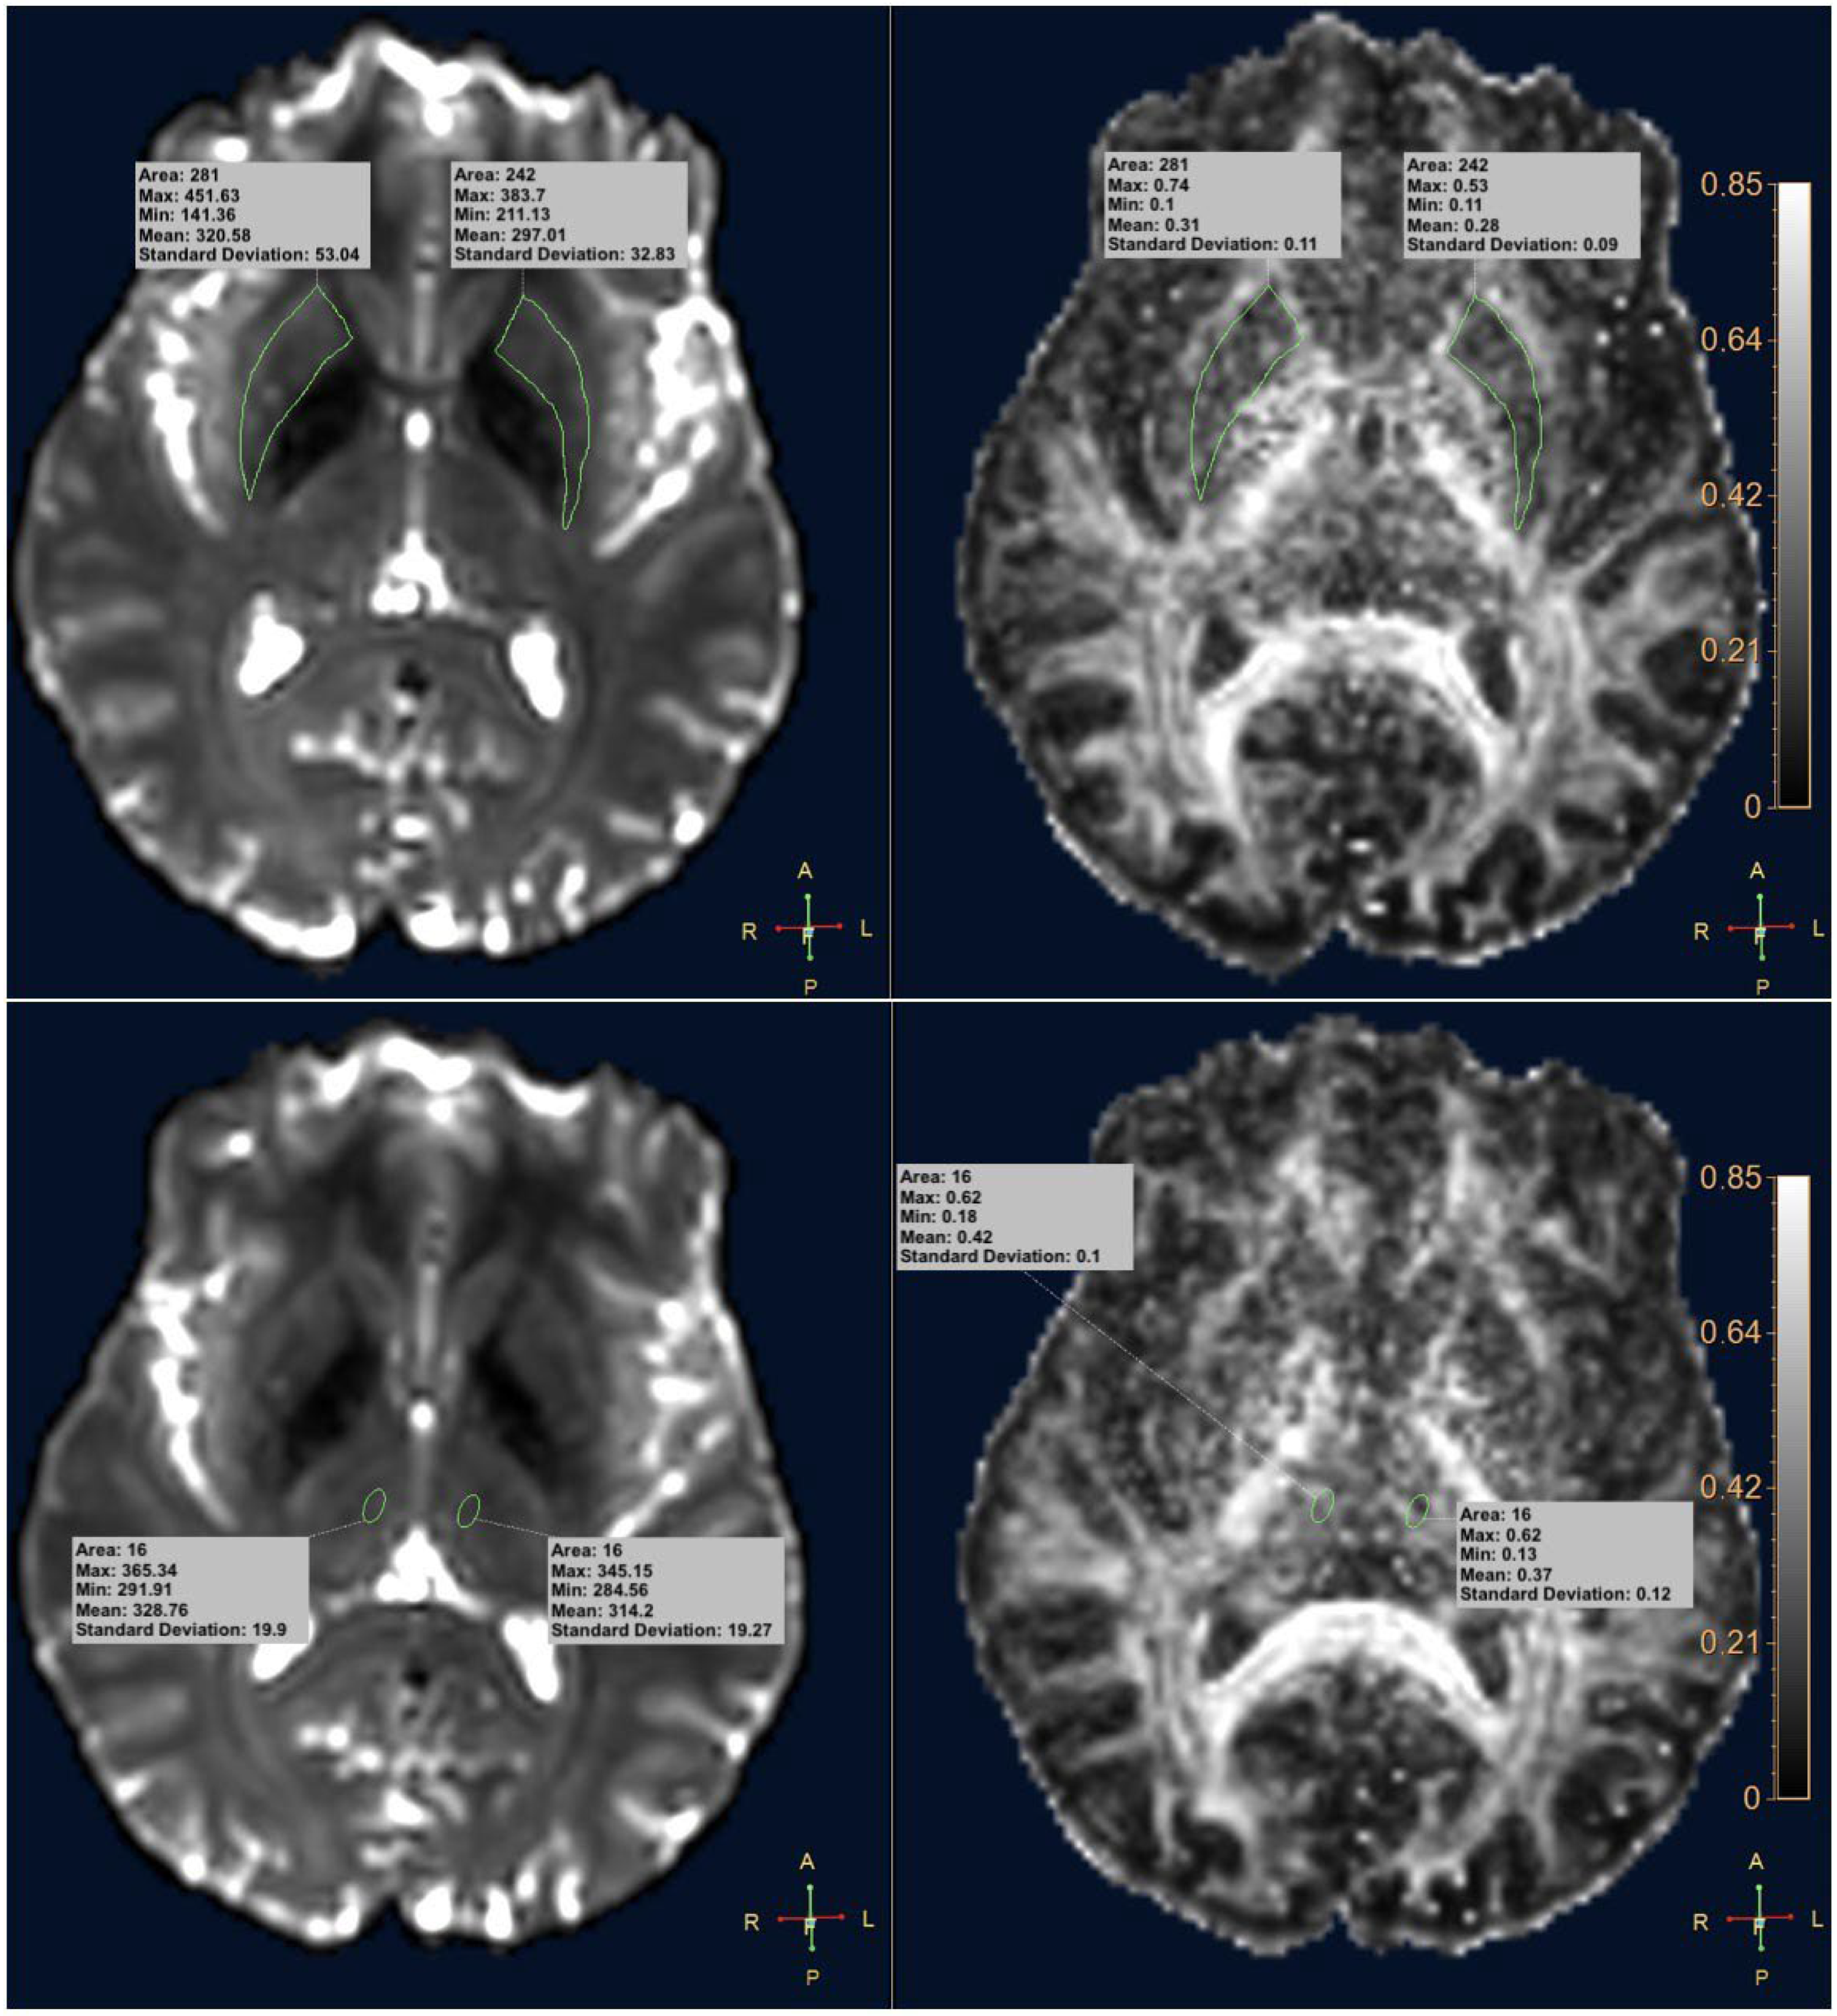

| Region | De Novo PD Patients | Control Subjects | p | |

|---|---|---|---|---|

| Right Putamen | Max | 0.711 ± 0.079 | 0.710 ± 0.067 | 0.985 |

| Min | 0.117 ± 0.038 | 0.113 ± 0.025 | 0.652 | |

| Mean | 0.366 ± 0.036 | 0.364 ± 0.033 | 0.839 | |

| Std | 0.121 ± 0.014 | 0.126 ± 0.012 | 0.185 | |

| Left Putamen | Max | 0.681 ± 0.084 | 0.689 ± 0.070 | 0.672 |

| Min | 0.115 ± 0.034 | 0.117 ± 0.033 | 0.868 | |

| Mean | 0.360 ± 0.035 | 0.362 ± 0.032 | 0.764 | |

| Std | 0.119 ± 0.013 | 0.011 ± 0.08 | 0.989 | |

| Right Thalamus | Max | 0.541 ± 0.077 | 0.586 ± 0.075 | 0.018 * |

| Min | 0.196 ± 0.061 | 0.213 ± 0.184 | 0.640 | |

| Mean | 0.359 ± 0.052 | 0.364 ± 0.033 | 0.045 * | |

| Std | 0.098 ± 0.024 | 0.114 ± 0.021 | 0.010 * | |

| Left Thalamus | Max | 0.541 ± 0.077 | 0.595 ± 0.085 | 0.012 * |

| Min | 0.207 ± 0.055 | 0.193 ± 0.049 | 0.295 | |

| Mean | 0.366 ± 0.040 | 0.374 ± 0.033 | 0.387 | |

| Std | 0.098 ± 0.024 | 0.114 ± 0.021 | 0.010 * |